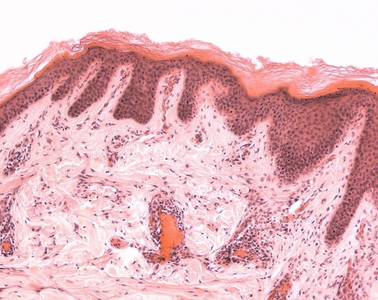

Präparat 97: Haare (Kopfhaut), Längsschnitt, H.-E.

An manchen Stellen senkt sich die Epidermis zu den sog. Haartrichtern ein, in denen die Haare stecken. Der "freie" Teil des Haares, der aus dem Rohr des Trichters herausragt, besteht aus dem Haarschaft (Scapus pili). Das Wachstum des Haares geht von der Haarzwiebel (Bulbus pili) aus, die in der Subkutis liegt. Hier beginnt die Haarwurzel (Radix pili).

Haartrichter

trichterförmige Erweiterung des Haarfollikels, hier münden die Talgdrüsen.

Scapus pili

(Haarschaft), vollständig verhornter Teil des Haares. Er besteht bei Terminalhaaren aus dem Mark (Medulla) und der breiteren Rinde (Cortex). Der in der Haut gelegene Teil des Haarschaftes wird umgeben von Cuticula, innerer und äußerer epithelialer Wurzelscheide sowie bindegewebiger Wurzelscheide.

Bulbus pili

(Haarzwiebel) glockenförmige Auftreibung der Haarwurzel, die die bindegewebige Haarpapille umfaßt.

Radix pili

Haarwurzel, geht aus der Haarzwiebel (Bulbus pili) hervor und ist noch nicht verhornt. Über die keratogene Zone geht die Haarwurzel in den verhornten Haarschaft über.